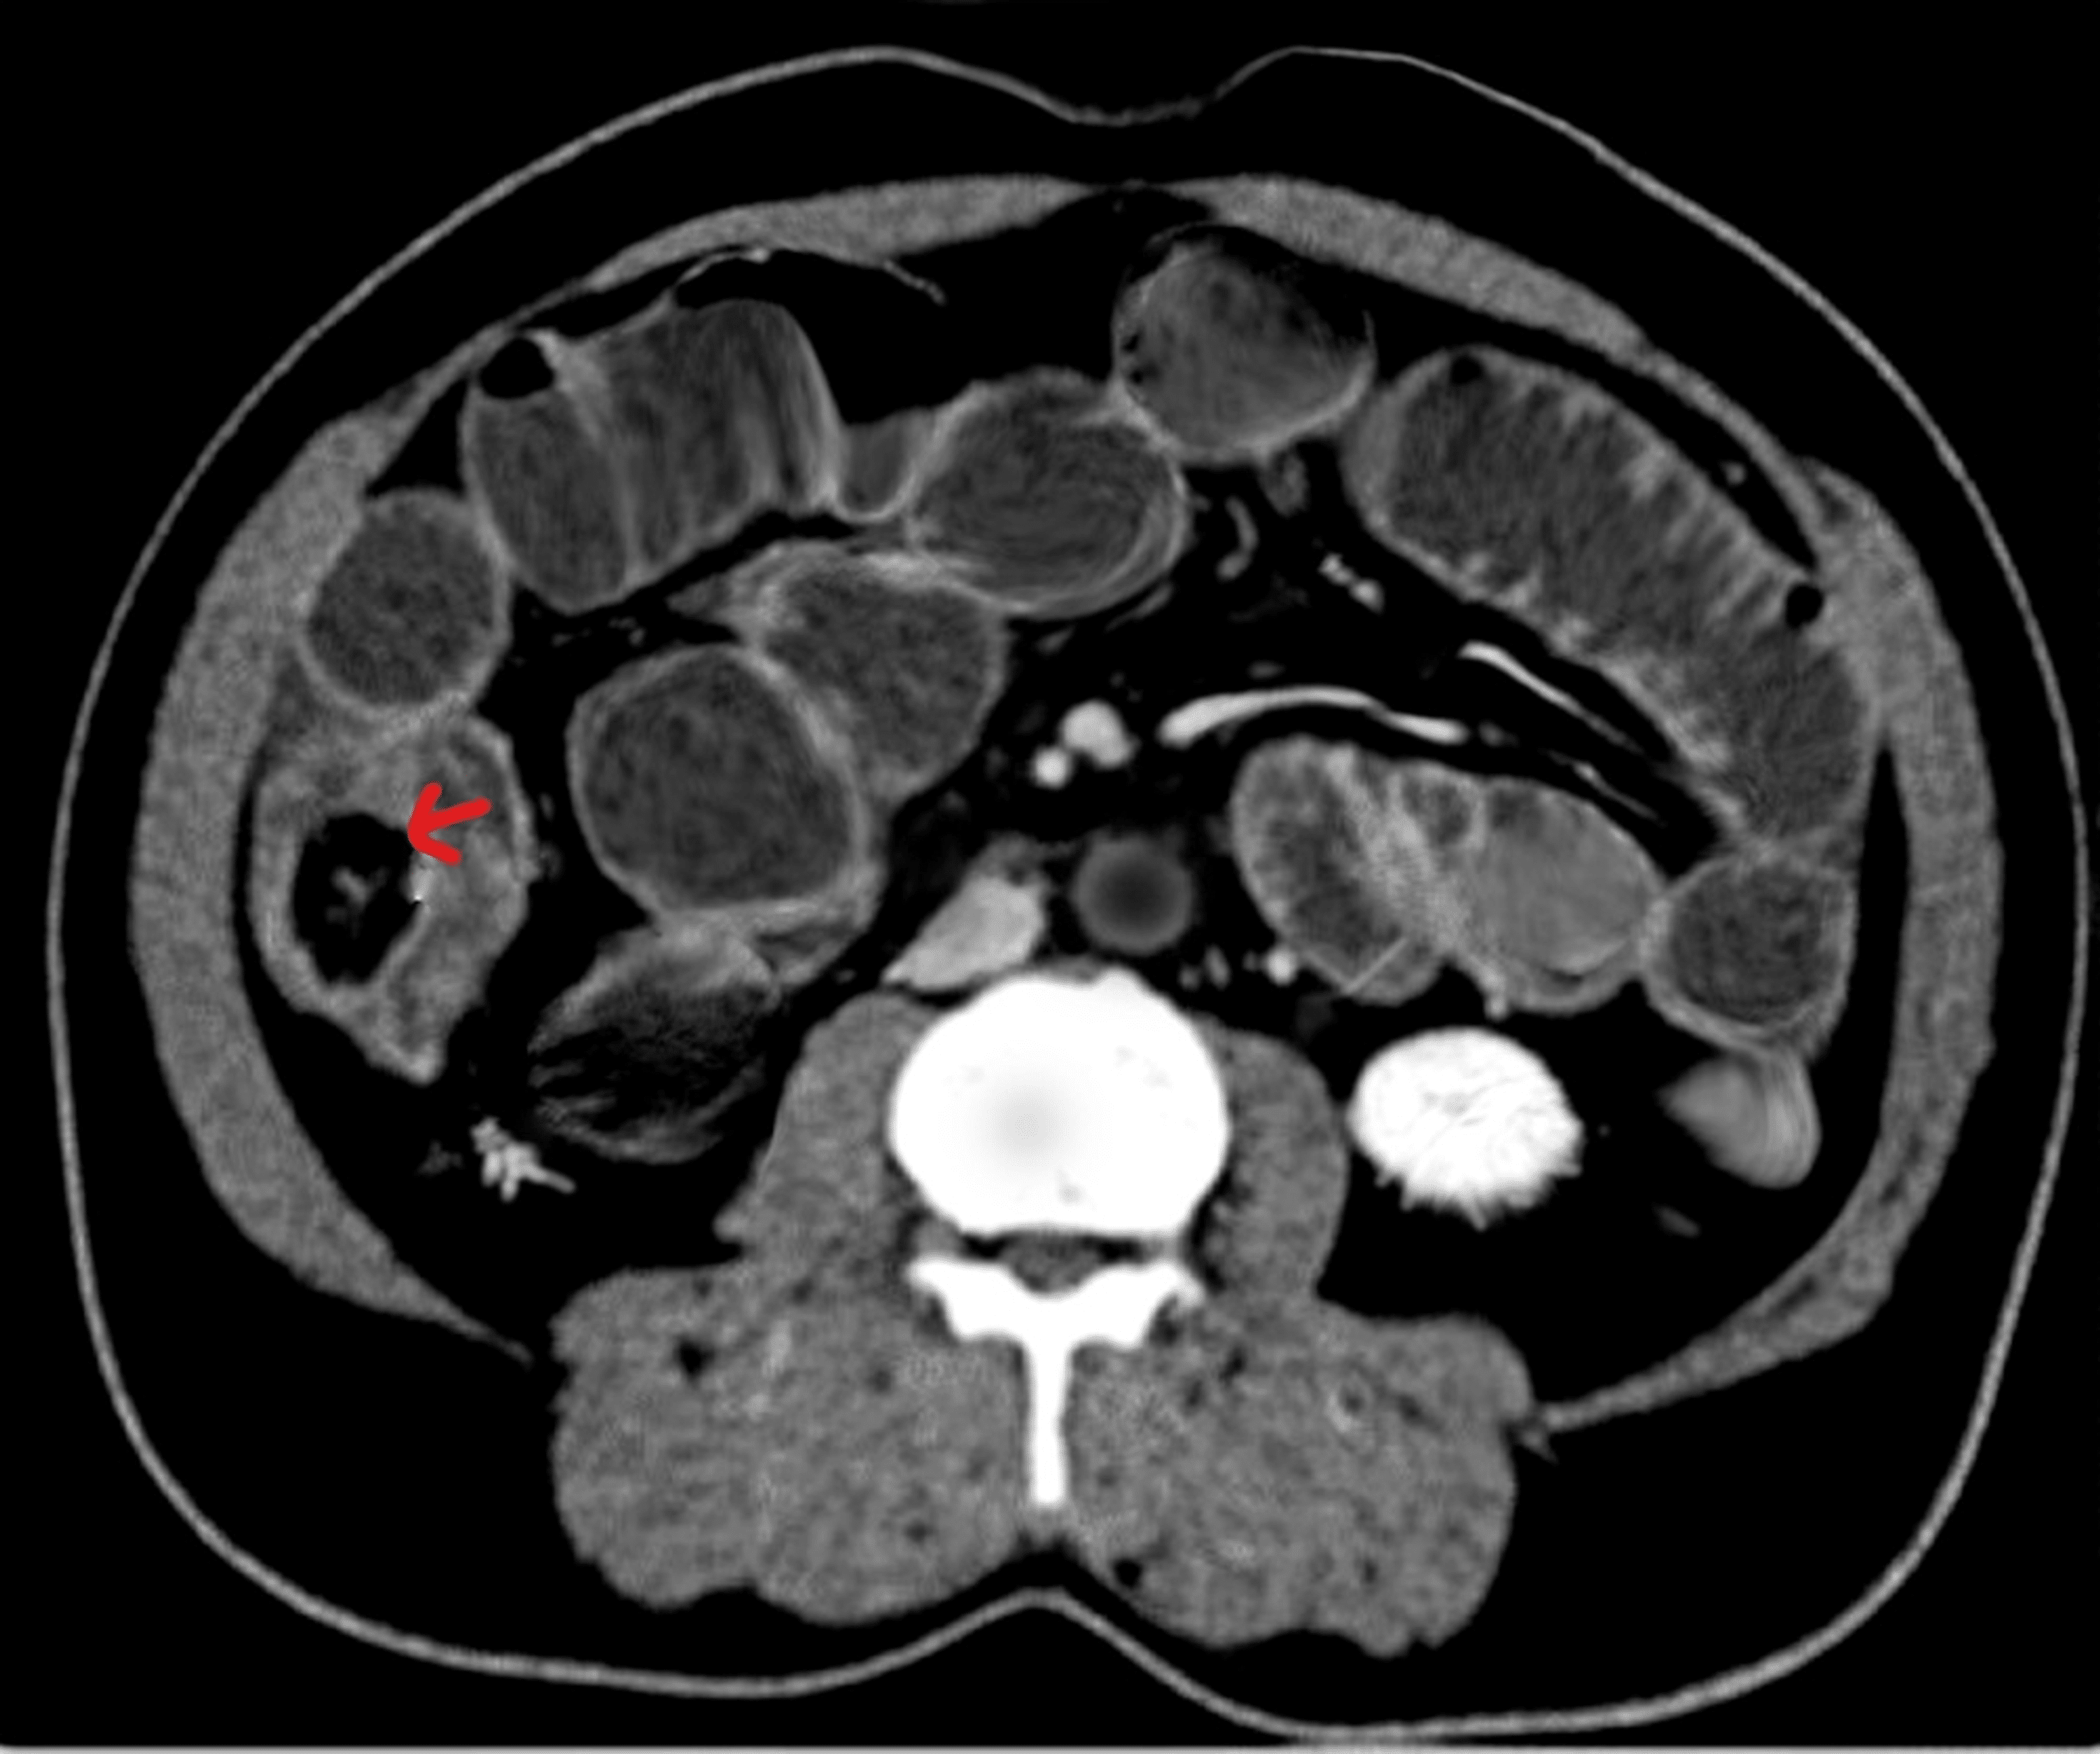

A Rare Case of Ileocecal Valve Stricture Gastroenterology

A Rare Case of Ileocecal Valve Stricture Gastroenterology How To Close Your Ileocecal Valve In this demonstration, dr nirala jacobi demonstrates a three minute maneuver anyone can try at home to free a stuck. A faulty ileocecal valve is the kind of digestive health issue that often goes unnoticed until another problem. I’ll explain the technique first and then later in the video i’ll get into why it malfunctions, some of the. One of. How To Close Your Ileocecal Valve.